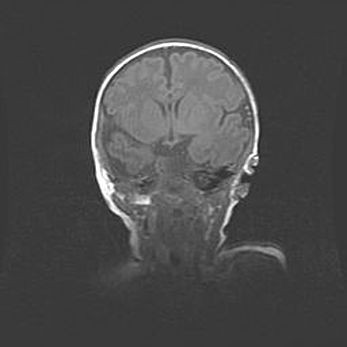

Множественные кисты обоих полушарий головного мозга, наибольшая из них в правой затылочной области. Ассиметричная атрофическая гидроцефалия.

Возраст: 7 месяцев

Вес: 5660 г

Пол: мужской

Окружность головы: 41,5 см

Срок гестации: 28-29 недель

Кисты головного мозга развиваются в результате многоочаговых некрозов вещества мозга и возникают вследствие перенесенной перинатальной инфекции, менингитов, энцефалитов, асфиксии, родовой травмы, расстройств мозгового кровообращения различного генеза. Образованию кист в веществе головного мозга плодов и новорожденных способствуют такие факторы, как высокое содержание в нем воды, недостаточная (или отсутствие) миелинизация и слабая астроглиальная реакция на повреждение.

Кисты могут сочетаться с гидроцефалией и другими поражениями головного мозга.